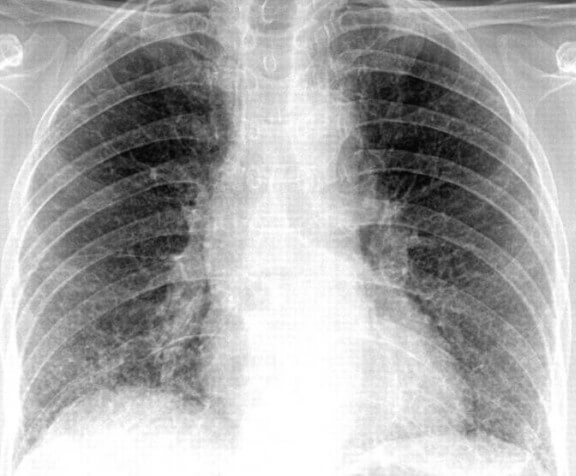

На снимках видно, что воспалительный процесс локализуется лобарно или сублобарно (то есть поражается доля легкого) с вовлечением плевры. Легочный рисунок при этом изменяется, а легочные корни расширяются. Видны застои жидкости в плевральной полости. С течением болезни тени на снимках становятся темнее.

Крупозная пневмония

- Крупозная пневмония. Наблюдаются изменения нормального легочного рисунка, жидкость в полости плевры, признаки инфильтрации одной из долей легкого, расширение корней. По мере развития воспалительного процесса выраженность изменений и интенсивность окраски затемнений усиливается.